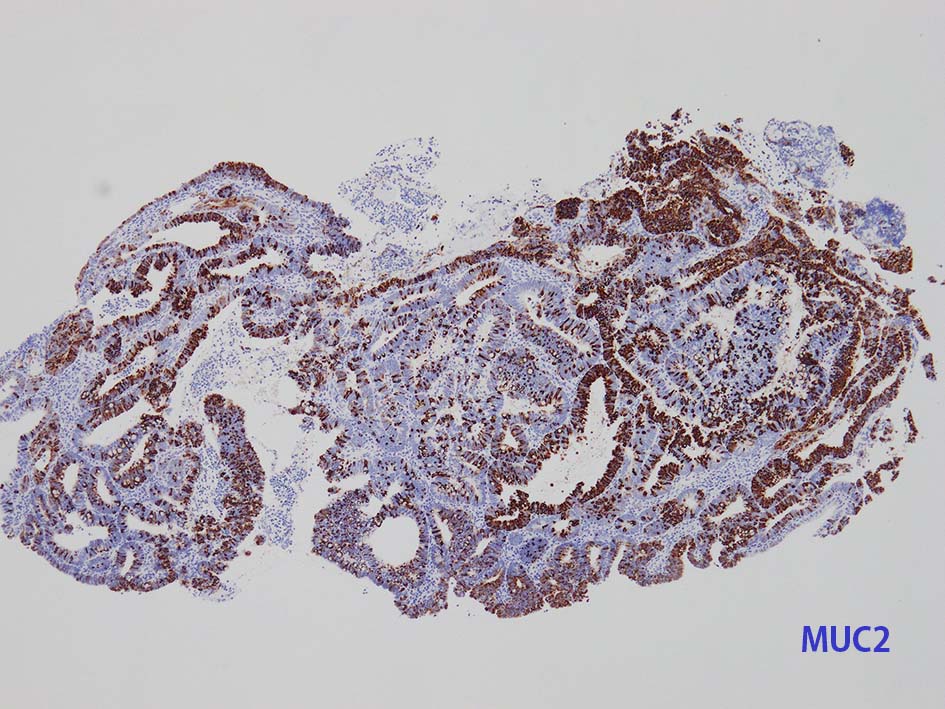

膀胱原発腺癌の診断に, サイトケラチン7および20、34βE12、トロンボモジュリン、CDX2およびβカテニンなどの免疫組織化学的パネルが提案されている。しかし他の原発部位に発生する腺癌と組織像だけでなく免疫組織化学的特徴が重複している. 原発性腺癌と転移性腺癌では予後や治療法が大きく異なるため, 鑑別診断において膀胱腺癌の診断を下す際には、臨床的、画像的、組織的、および免疫組織化学的な相関を注意深く確認する必要がある。

mark-g.gif 免疫染色